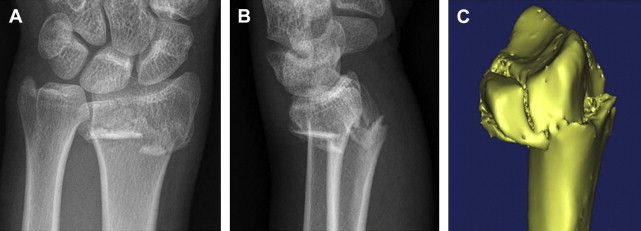

∗∗ Surgical Notes: These groups of patients are best assessed with a computerized tomography (CT) scan and 3-dimensional (3D) images to evaluate joint step-offs, distal radioulnar joint (DRUJ) involvement, and direction of displacement of multiple fragments ( Fig. 1 ).

The aforementioned indications provide a quick reference for surgeons, from experienced to trainees, in emergency settings in the author’s unit and reflect their practice guidelines. AO classification is determined and treatment selected in the making of the diagnosis, evaluation of images, and discussed among the surgical team. Three-dimensional image reconstruction is used for accurately locating fracture fragments (see Fig. 1 ).